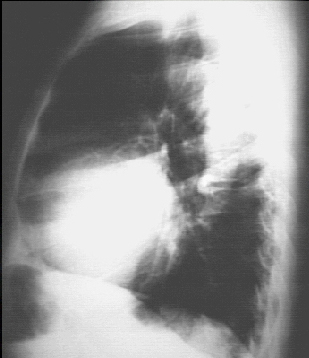

Lateral view

The PA view demonstrates cardiomegaly, as evidenced by a cardiothoracic ratio greater than 50%. Note also the increased inferolateral cardiac border that is consistent with ventricular enlargement due to volume overload. The ascending, transverse, and descending aortic shadows are also prominent. The lateral view shows left ventricular enlargement, as evidenced by posterior displacement of the left ventricular shadow.